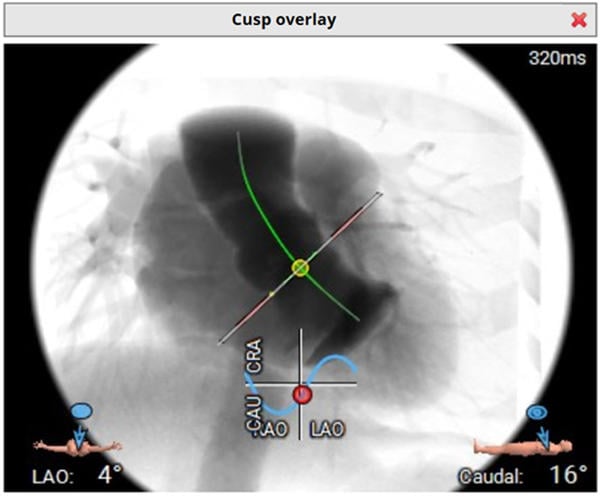

Computed tomography

- 68-year-old woman with symptomatic aortic valve stenosis and tricuspid valve anatomy